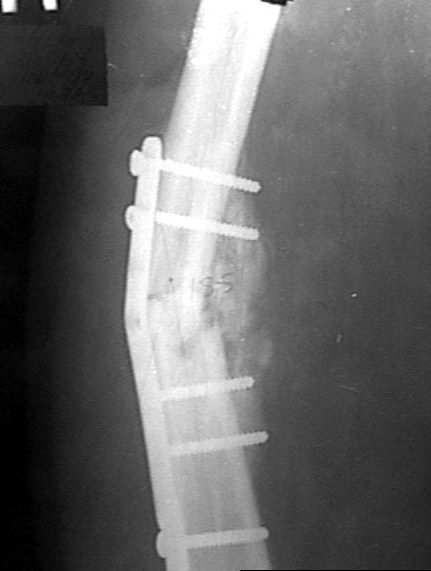

Диагноз: двойной оскольчатый перелом правого бедра в с/3 и н/3 со смещением, открытый оскольчатый перелом правой большеберцовой кости в с/3 со смещением двойной перелом малоберцовой кости. Оперирован проведена открытая репозиция, остеосинтез двумя пластинами бедренной кости, иммобилизация кокситной повязкой. На контрольных рентгенограммах от 21 01 04 имеется: несостоятельность остеосинтеза бедренной кости в в/3 выраженная угловая деформация; консолидирующийся перелом большеберцовой кости со смещением по длинне и выраженной вальгусной деформацией. Родственникам рекомендовали оперативное лечение. Больного доставят на осмотр 28.01.04, обдумываем способы лечения. Оперативное лечение планируем в два этапа, вначале на бедре, затем на голени. На бедре- удаляем верхнюю пластину, проводим остеотомию по линии верхнего перелома, проводим репозицию, остеосинтез пластиной с фиксацией верхнего, среднего и нижнего фрагментов.На голени-мнения разделились:- можно наложить аппарат внешней фиксации на голень, провести остеотомию б/берцовой кости в зоне перелома между проксимальным отломком и осколком, остеотомию малоберцовой кости, провести постепенную репозицию, тибиализацию (рисунок 3).-или провести остеотомию по линии перелома большеберцовой кости, репонировать и фиксировать пластиной. Новосибирская областьг Куйбышев ЦРБСергей Зырянов

Привет Сергей! Разделять вмешательства на этапы рационально, если соматический статус больного нестабильный или Ваши анестезиологи не смогут по той или иной причине обеспечить вмешательство в один этап. Я бы предложил вмешательство в один этап: на бедре ресинтез "нормальной пластиной" на 18-20 винтах с дистальным клинком, выбросив "негодный металлолом"- все равно придется металл убирать, даже если планировать внутрикостный синтез стержнем с блокированием, на голени аппарат по классической схеме без перемещения фрагмента м\б кости. Периоперационное обеспечение крайне важно: спинально-эпидуральная анестезия с пролонгированием обезболивания, кровосбережение, профилактика ТЭЛА и инфекции классические. Судя по

рентгенограммам -проблем с остеорепарацией у больного нет - проблемы с некачественным остеосинтезом привели к данной ситуации. Желаю успеха и удачи.